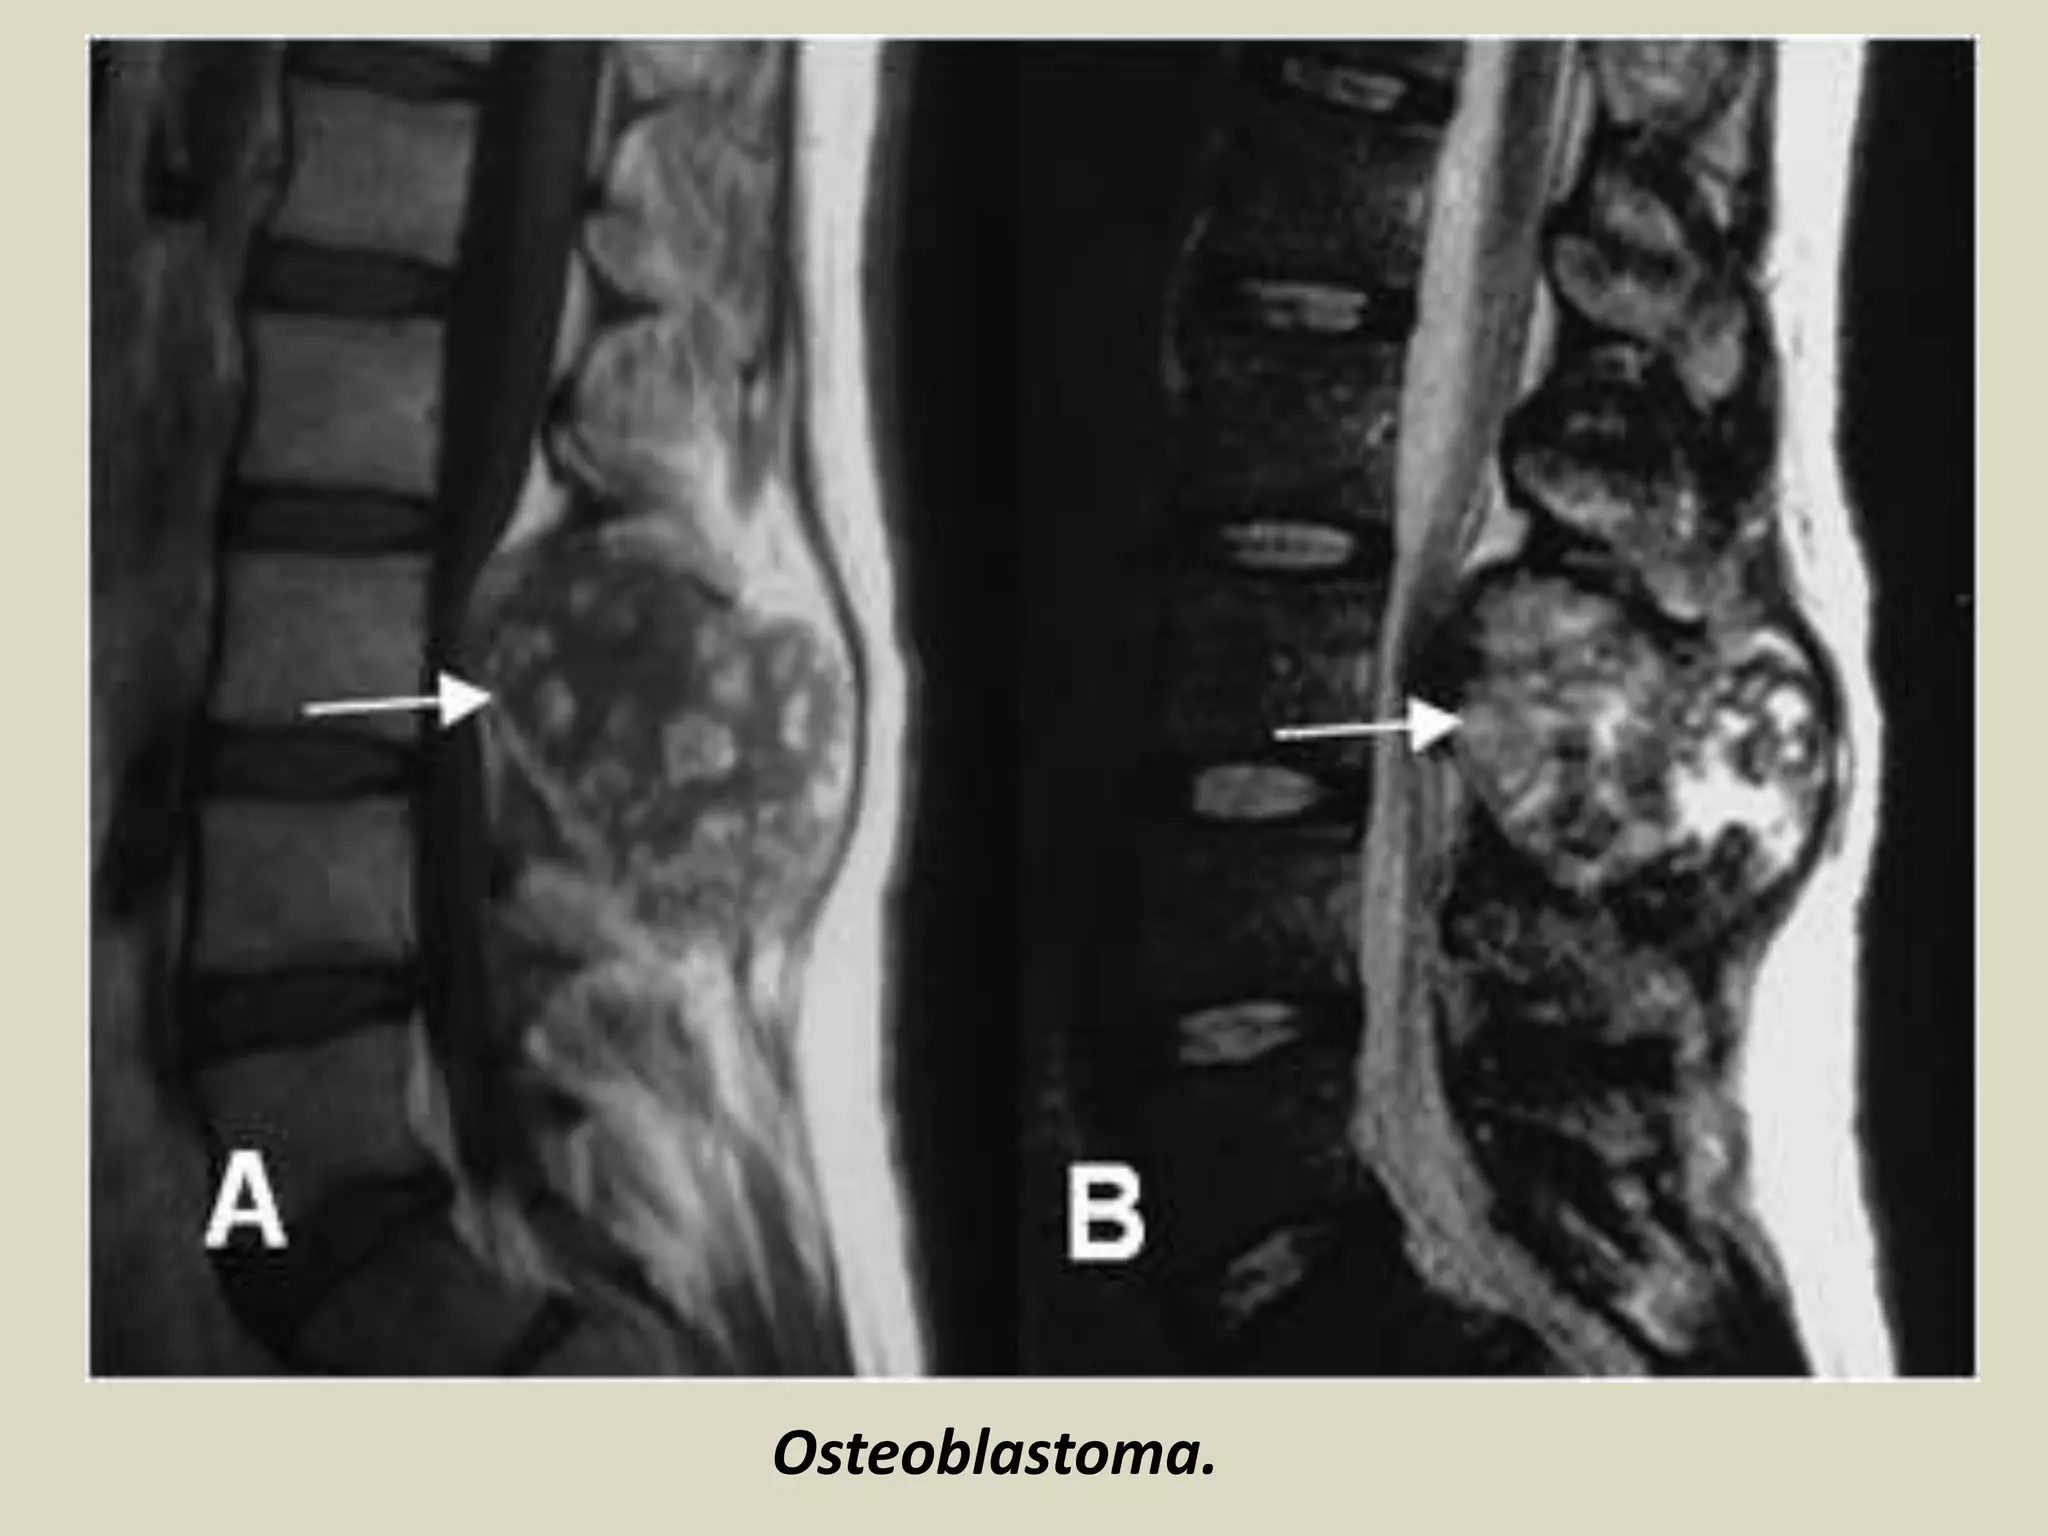

-OSTEOBLASTOMA

Definition:

- Benign bone forming neoplasm producing woven bone

spicules bordered by prominent osteoblasts (osteoid

osteoma measuring more than 2.0 cm)

Epidemiology:

- About 1% of bone tumors

- Age: 10-30 y/o ( male teenagers)

- Male: Female ratio 2.5:1,

Sites of involvement:

- Predilection for the spine (40-55% of cases)

- Other common sites femur and proximal tibia

- Cementoblastoma of jaw is considered osteoblastoma

and is attached to the root of tooth.

Clinical findings:

- Osteoblastoma of spine may cause back pain, scoliosis

and nerve root compression.

- Jaw lesion may produce tooth pain.

- Aspirin does not relieve pain after long therapy.

Imaging:

- Lytic well circumscribed oval or round defect

-Almost always confined by a periosteal shell of reactive bone.

Osteoblastoma

Osteoblastoma.